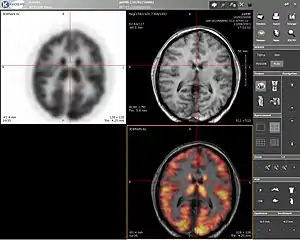

Computer screenshot showing a PET image (upper left), MRI image (upper right) and the combined PET-MRI image where PET data is overlaid over the MRI data (lower right) | |

Positron emission tomography–magnetic resonance imaging (PET–MRI) is a hybrid imaging technology that incorporates magnetic resonance imaging (MRI) soft tissue morphological imaging and positron emission tomography (PET) functional imaging.[1]